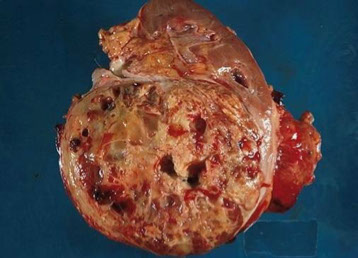

Nephroblastoma (Wilms tumor)

References:

1. Dr Z's renal path notes

2. Robbins

3. AP board review books

4. Xiao X et al. Practical Applications of Immunohistochemistry in the Diagnosis of Genitourinary Tumors. Arch Pathol Lab Med. 2017; 141:1181-1194